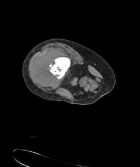

59 year old female complains of knee pain for two months

ESR 112mm/hr

CRP 156 mg/l

WBC 14.6

Zoom image: Radiological image Radiological image.